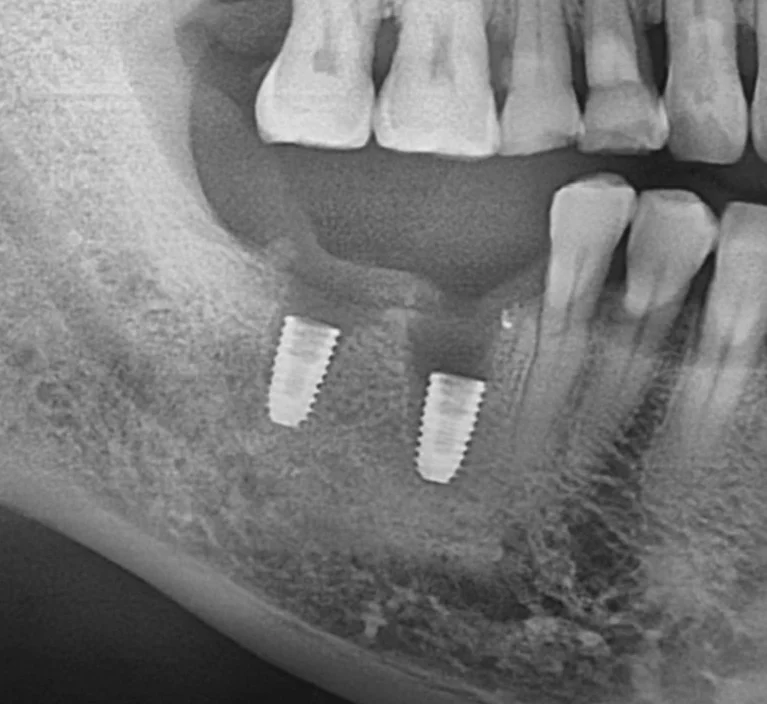

결국 두 임플란트 모두 제거한 뒤, 위 사진과 같이 본원에서 다시 임플란트 치료를 진행하게 되었습니다.